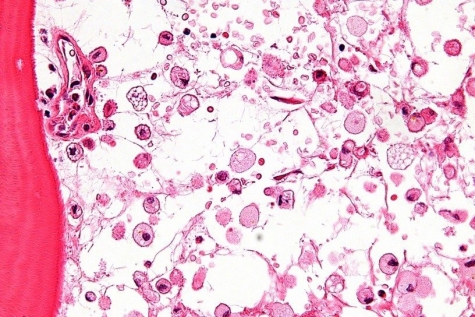

La Malattia di Gaucher è una condizione rara ed ereditaria con una frequenza intorno a 1 su 40.000 persone. A causa della carenza di un enzima, la beta-glucosidasi acida (glucocerebrosidasi), che ha il ruolo di scindere una molecola di natura lipidica, la malattia porta un accumulo di lipidi nelle cellule denominate appunto di Gaucher. Questo provoca l'ingrossamento della milza e del fegato con anemia, ematomi, sanguinamento eccessivo, ma anche osteoporosi o alterazioni ossee. La malattia di Gaucher fu descritta per la prima volta nel 1882, ma gli studi clinici sono partiti molti anni dopo. Basti pensare che solamente nel 1984, grazie alla madre di un bambino statunitense e a un gruppo di ricercatori, si iniziò la sperimentazione della terapia con l'enzima mancante.